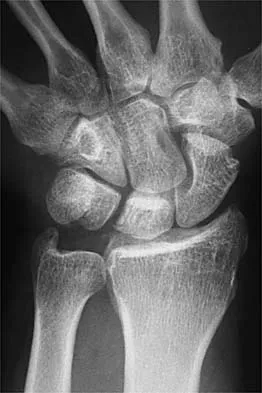

Question 70 High Yield

A 54-year-old woman with idiopathic carpal tunnel syndrome undergoes open carpal tunnel release with a flexor tenosynovectomy. The pathology from the tenosynovium is likely to show

Detailed Explanation

The tenosynovium excised at the time of a carpal tunnel release for idiopathic carpal tunnel syndrome rarely shows signs of acute or chronic inflammation. Fibrosis, edema, and vascular sclerosis are the most common histologic findings. A tenosynovectomy with a carpal tunnel release usually is not necessary in the treatment of idiopathic carpal tunnel syndrome. Shum C, Parisien M, Strauch RJ, et al: The role of flexor tenosynovectomy in the operative treatment of carpal tunnel syndrome. J Bone Joint Surg Am 2002;84:221-225. Fuchs PC, Nathan PA, Myers LD: Synovial histology in carpal tunnel syndrome. J Hand Surg Am 1991;16:753-758.